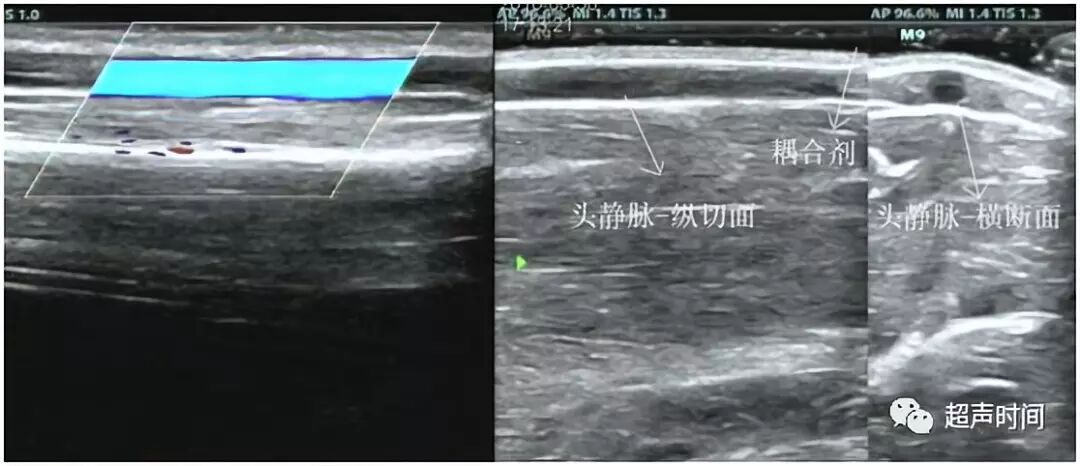

静脉:头静脉、贵要静脉、肘正中静脉位于浅层,皮肤与肌肉之间,无动脉伴行,头静脉走行于桡侧,贵要静脉走行于尺侧。肘正中静脉为一短粗的静脉干,在肘窝处连接头静脉和贵要静脉(视频 1 和图 1 和图 2)。

图 1

动静脉内径:经血管纵向和横断面测量(图 3 和图 4),测量时应尽量与血管走行保持平行或垂直,避免夸大或缩小管腔内径。应在报告中应说明测量的大致位置,或用标记笔在体表标记。

图 3 和图 4

测量浅表静脉(如贵要静脉、头静脉)时,患者应保持静息状态,在其体表多涂抹耦合剂,探头悬空不能压迫静脉,否则影响其内径评估。